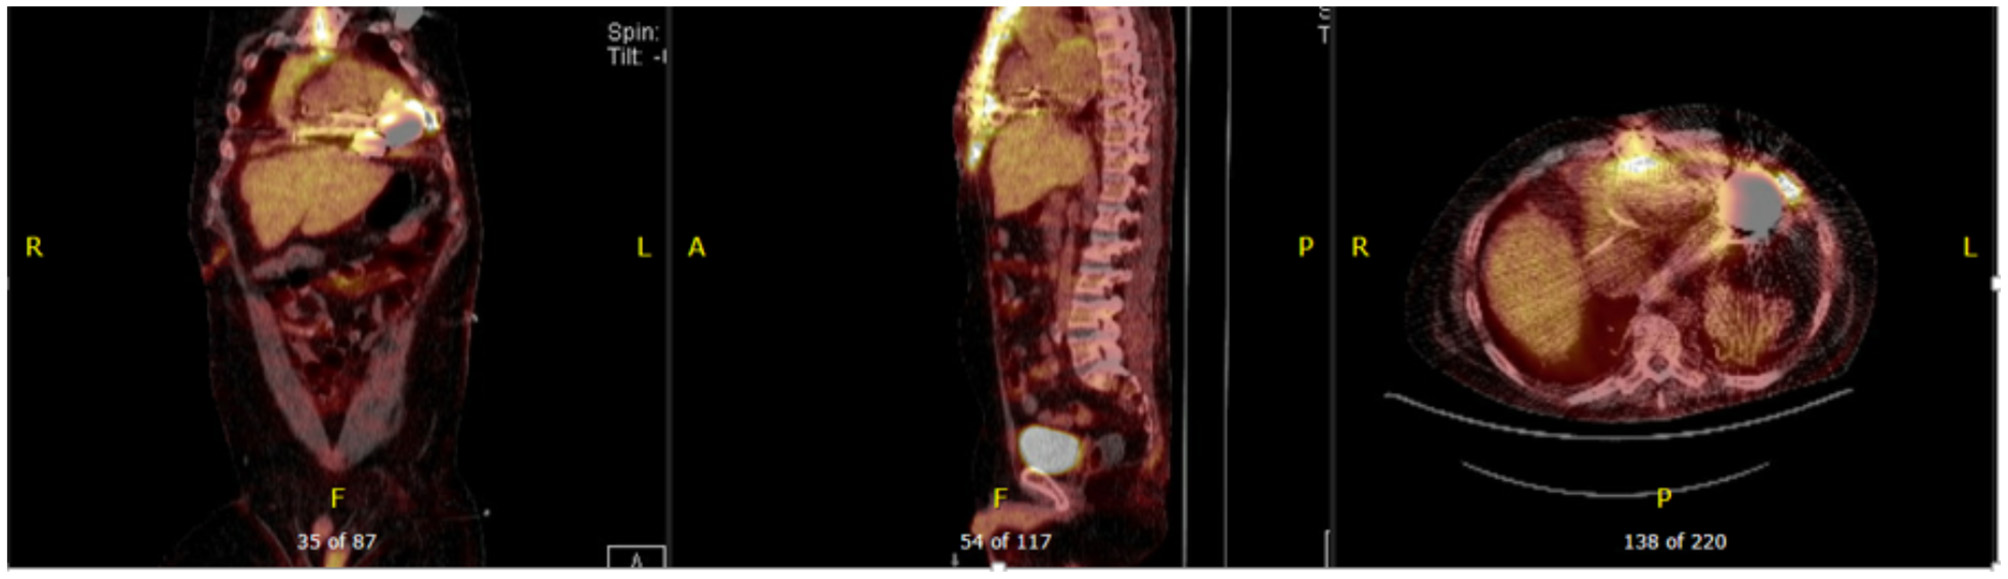

Figure 6

Forty seven year-old male with ischemic cardiomyopathy s/p LVAD (Heart Mate 3) presented with suspected DLI, with wound cultures positive for Candida Albicans. 18F-FDG PET-CT showed FDG activity in the pericardium, mediastinum, surrounding LVAD pump, driveline and sternum consistent with deep and superficial LVAD infection. He was managed with systemic lifelong antifungal therapy.